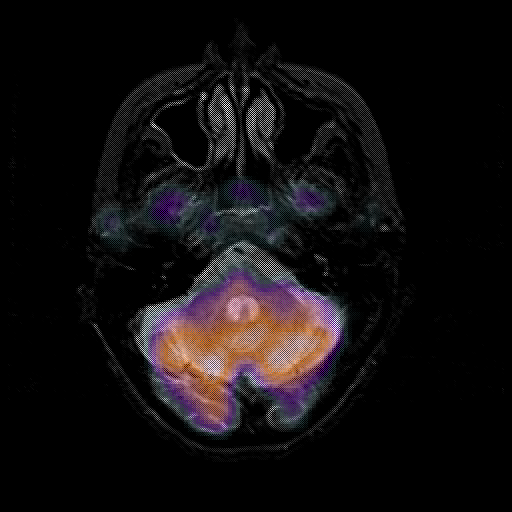

overlay 1: Slice 13

Slice 13

MRCBFCBF with